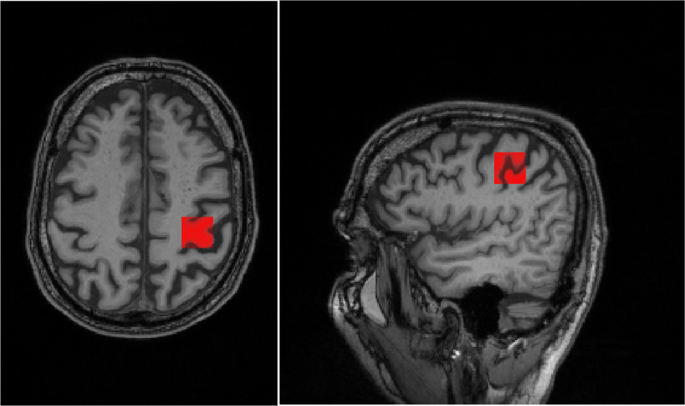

Data acquisition

All participants were scanned on a 3 T Siemens Trio (Erlangen, Germany) using a 32-channel head coil. A T1-weighted anatomical MPRAGE scan (TR/TE = 2420/4.6 ms, 1 mm isotropic resolution), was first acquired, and used to guide placement of a 2.5 × 2 × 2 cm MRS voxel in the occipital lobe, and a 2 × 2 × 2 cm MRS voxel in the hand area24 of the primary motor cortex (see Fig. 2).

Example of voxel placement in the hand area of the primary motor cortex overlaid on MPRAGE T1.